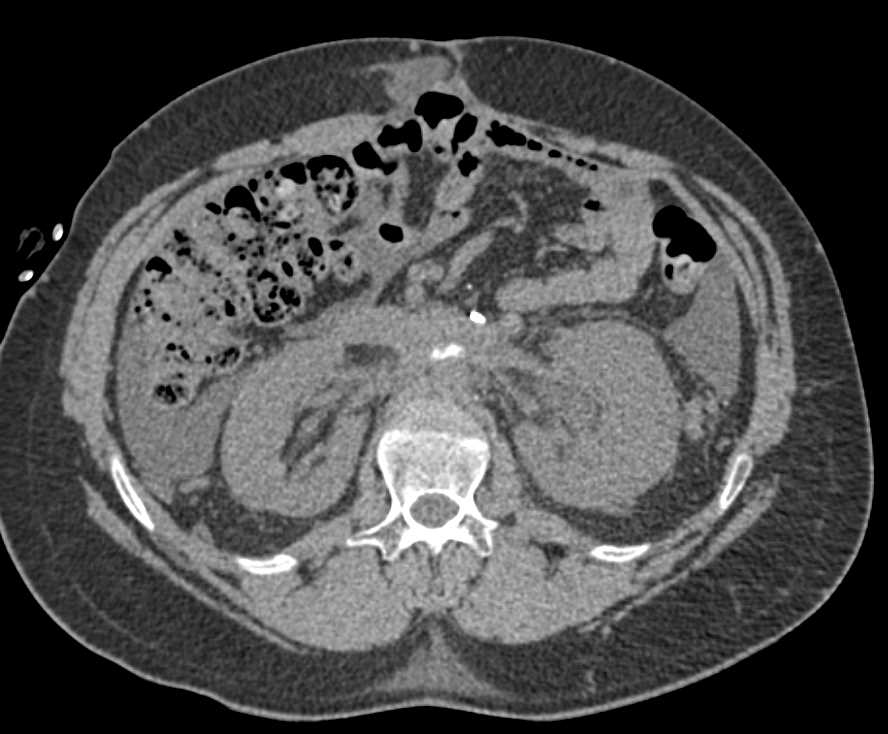

Active Bleed Right Superficial Femoral Artery (SFA) with Thigh Hematoma